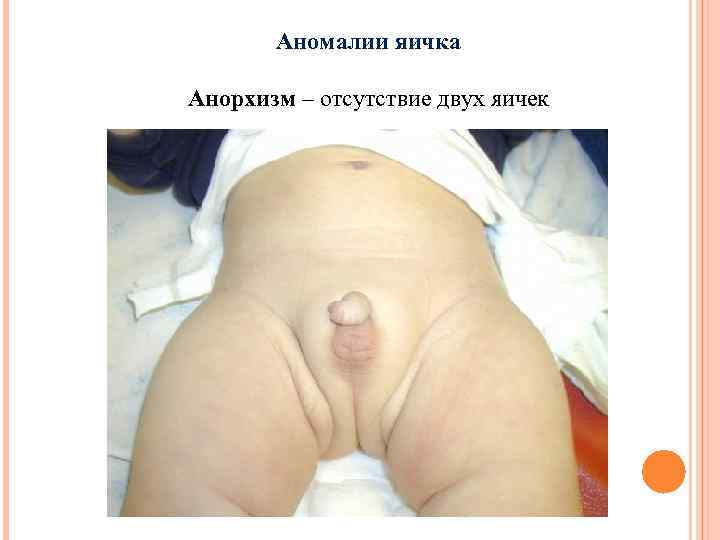

Аномалии яичка Анорхизм – отсутствие двух яичек

Аномалии яичка Анорхизм – отсутствие двух яичек